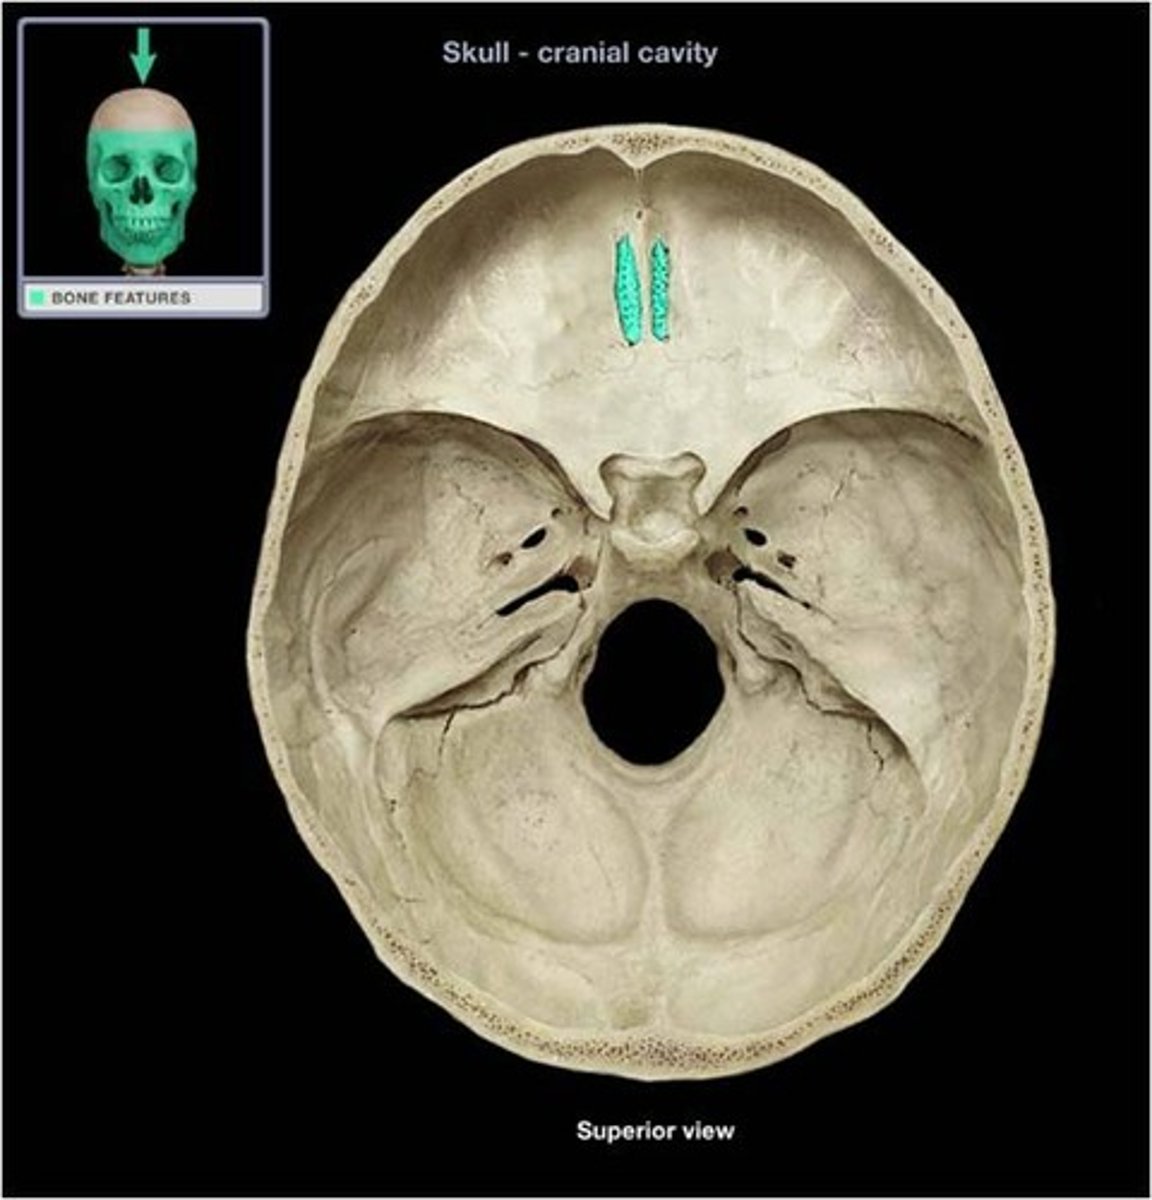

Cribiform plate

Crista galli